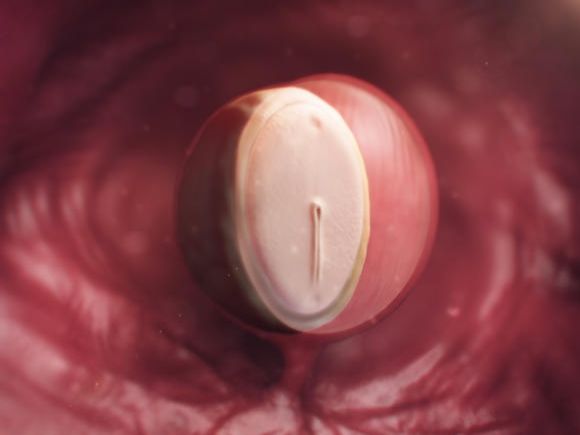

4. týden těhotenství

Maminka

V tomto týdnu těhotenství už můžete bezpečně zjistit, že jste těhotná. Těhotenský tes t je ale nejlepší provádět až jeden...